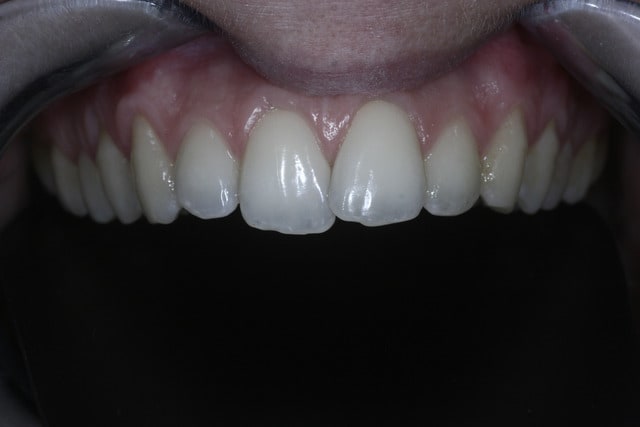

Cett jeune patiente refuse l'ODF "classique" mais veut faire qqchose pour corriger le chevauchement.

QQun pourrait me dire comment faire, je pensais un traitement comme le propose Danche mais pourriez-vous me préciser les références du matériel utilisé et la façon de faire ?

Matériel et méthode ainsi que cas cliniques publiés dans "L'Orthodontie Française" - Vol 80 - N°3 - Septembre 2009- p.305 à 312.

Utilisation universelle...:

http://www.vetortho.net/article-29146775.html